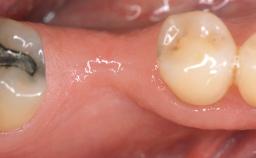

A 30-year-old woman was referred by her general dentist for evaluation of an esthetic complication related to previous implant treatment for congenitally missing maxillary lateral incisors. The patient’s chief complaint was the inadequate esthetic appearance of her smile. The case demonstrates the use of a combined approach to achieve optimal results. Two different flap designs - a tunnel technique and a coronally advanced flap - are employed based on the surgical objectives for the affected site.

Soft Tissue Anatomy Intact Defective